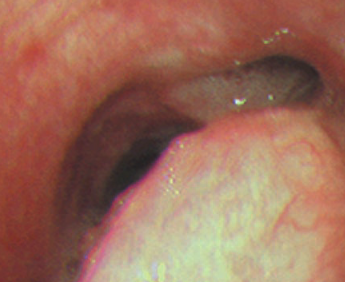

Polychondrite Atrophiante (Récidivante)

- Maladie auto-immune rare: Inflammation des cartilages

- Destruction des cartilages de l’oreille, nez, articulaires, larynx…

- Epaississement lisse de la tracée

- Epargne la zone postérieure

- Calcifications grossières plutôt parallèles